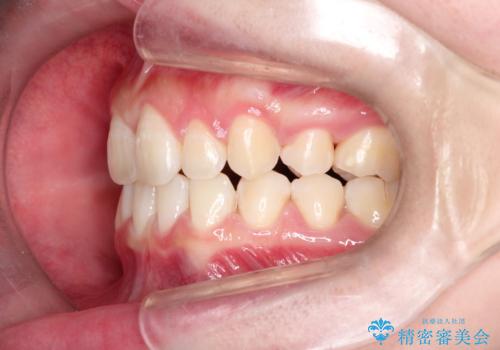

- 前歯のガタガタを主訴に来院されました。

抜歯を行い、インビザラインにて治療を完了しております。